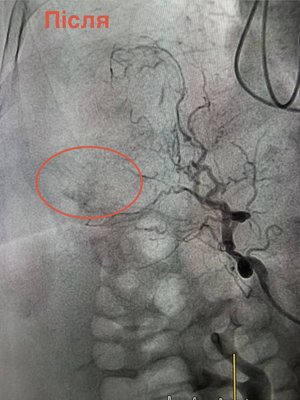

Відкрита операція — неможлива, але завдяки ендоваскулярній хірургії та ангіографії вдалося зупинити кровотечу методом емболізації судини.